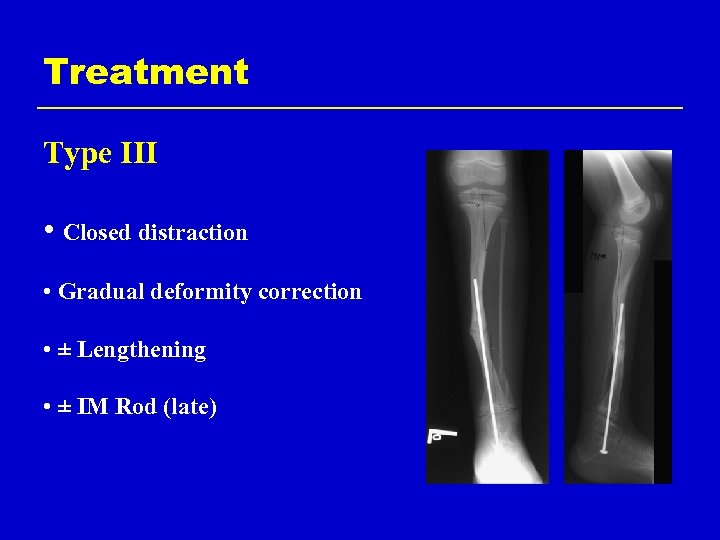

Treatment Type III • Closed distraction + compression • Gradual deformity correction • ± Lengthening • ± IM Rod (late)

Treatment Type III • Closed distraction • Gradual deformity correction • ± Lengthening • ± IM Rod (late)